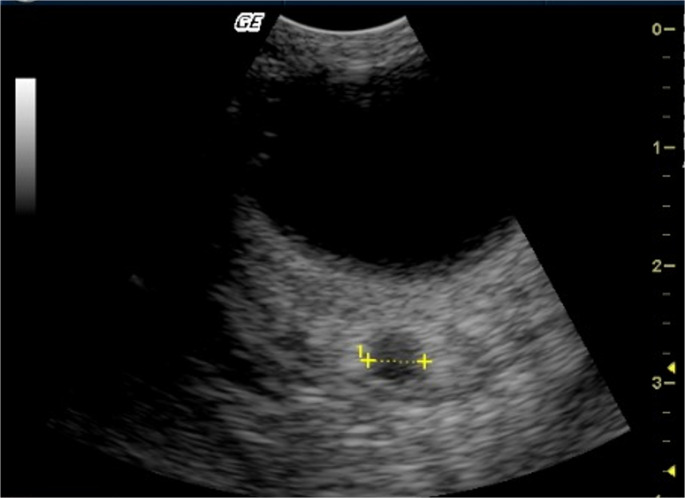

Methods: IOP measurements were performed using rebound tonometer, and transpalpebral ultrasonographic assessment of the ONSD was conducted. CSF samples were collected, and E2 and P4 levels were quantified using enzyme-linked immunosorbent assay (ELISA). Multiple regression analysis was conducted to assess the relationships among the variables.

Results: Multiple regression analyses on dogs found that the level of cerebrospinal fluid estradiol level (CSF-E2) significantly influenced left (L) ONSD (p = 0.0421, R² = 0.1551) and right (R) ONSD (p = 0.0216, R² = 0.1938). Systolic blood pressure (SBP) was a significant independent variable for left intraocular pressure (LIOP) (p = 0.0122, R² = 0.2261), while body weight was a significant predictor for right intraocular pressure (RIOP) (p = 0.0008, R² = 0.3679).

Conclusions: This study revealed that CSF-E2 levels exert a significant influence on ONSD in dogs, whereas no direct association was observed between IOP and ONSD. These findings underscore the notion that ONSD is modulated not only by hemodynamic mechanisms but also by hormonal regulation.